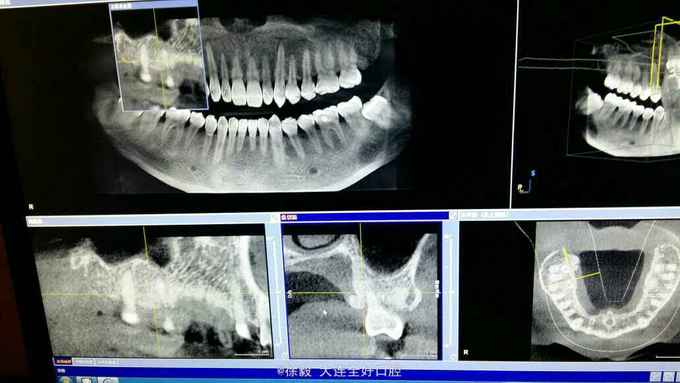

患者男性,40岁,体健。无遗传史。 患者前天就诊洗牙,治疗过程中发现上颌左上34颊侧,67舌侧明显有凸起,手触硬,无波动,无明显疼痛。右侧对应位置也有增生,但是凸起程度小。下颌前牙区舌侧也有黄豆大小凸起。 拍颌面ct和曲断检查,上颌左右45处有明显阴影区,右上45区在映像沙化过程中,骨密度透光变化明显。上颌左右67位置颊侧有致密骨映像,很像骨增生。 患者怀疑有没有恶性倾向,希望会诊一下。